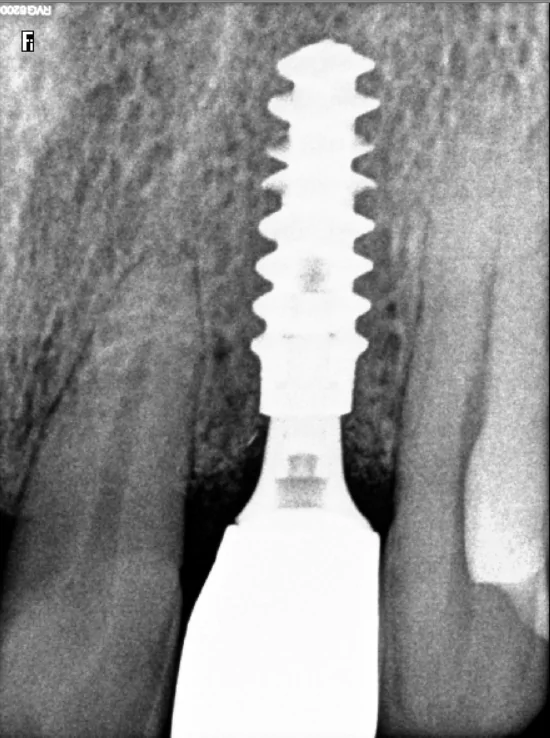

Standard Implant

Used when there’s enough bone in the area. A single titanium implant is placed in the jaw, followed by a custom crown once it heals. The tooth functions and looks natural.